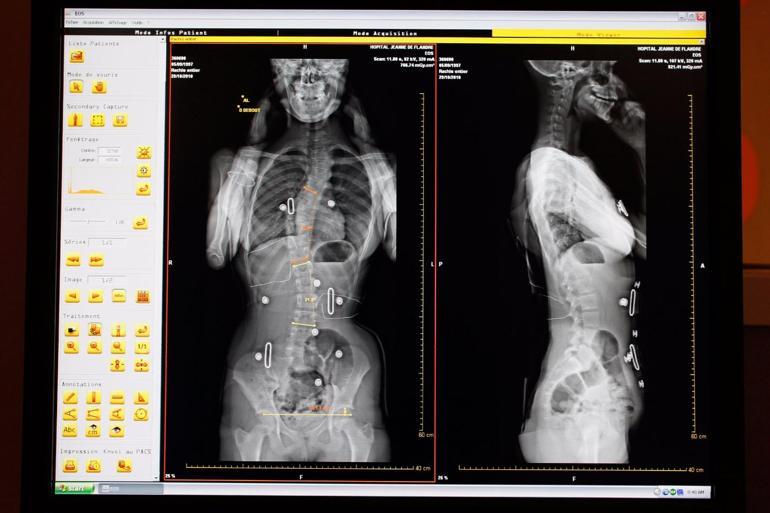

Skolyoz omurganın kişiye önden bakıldığında görülen eğriliğidir bu omurga eğriliği farklı yönlerde ve bir kaç tane de olabilir. 50 derece özelliklede 70 derece üzeri eğrilikler erişkin yaşlarda oldukça az olmasına karşı ilerleme gösterirler. İskelet gelişiminin tamamlanıp büyümenin durduğu yaşlarda ilerleme ileri eğrilikler hariç durur. çoğunlukla skolyoz hastalığı kişinin sırtında ağrılara eğri durmasına vertebra sayısına ve eğrilik.